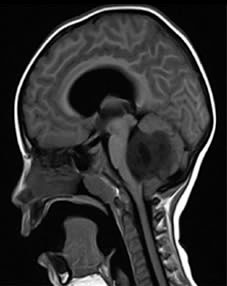

analisis-de-intervencion-interdisciplinaria-en-ninos-con-tumor-de-la-fosa-posterior.jpg

El tumor de la fosa posterior es una neoplasia que ocupa la fosa craneal posterior que se encuentra limitada por el clivus, en la zona inferior por el foramen mágnum, posterior por la concha del hueso occipital y a sus laterales por la porción petrosa mastoidea del hueso temporal y arte del hueso parietal (Fajardo,2001). Este tumor es el segundo tipo de cáncer infantil más común; representa en la población pediátrica el 48% del total de esta y su incidencia es de 4,5 por cada 100.000 niños. Afecta en mayor parte al género masculino con 57% del grupo poblacional reportado. Dosterceraspartes aproximadamente, de todos los tumores intracraneales que aparecen en niños entre 2 y 12 años de edad, son los infratentoriales pertenecientes a la zona posterior del cerebro (Cano, 2010).